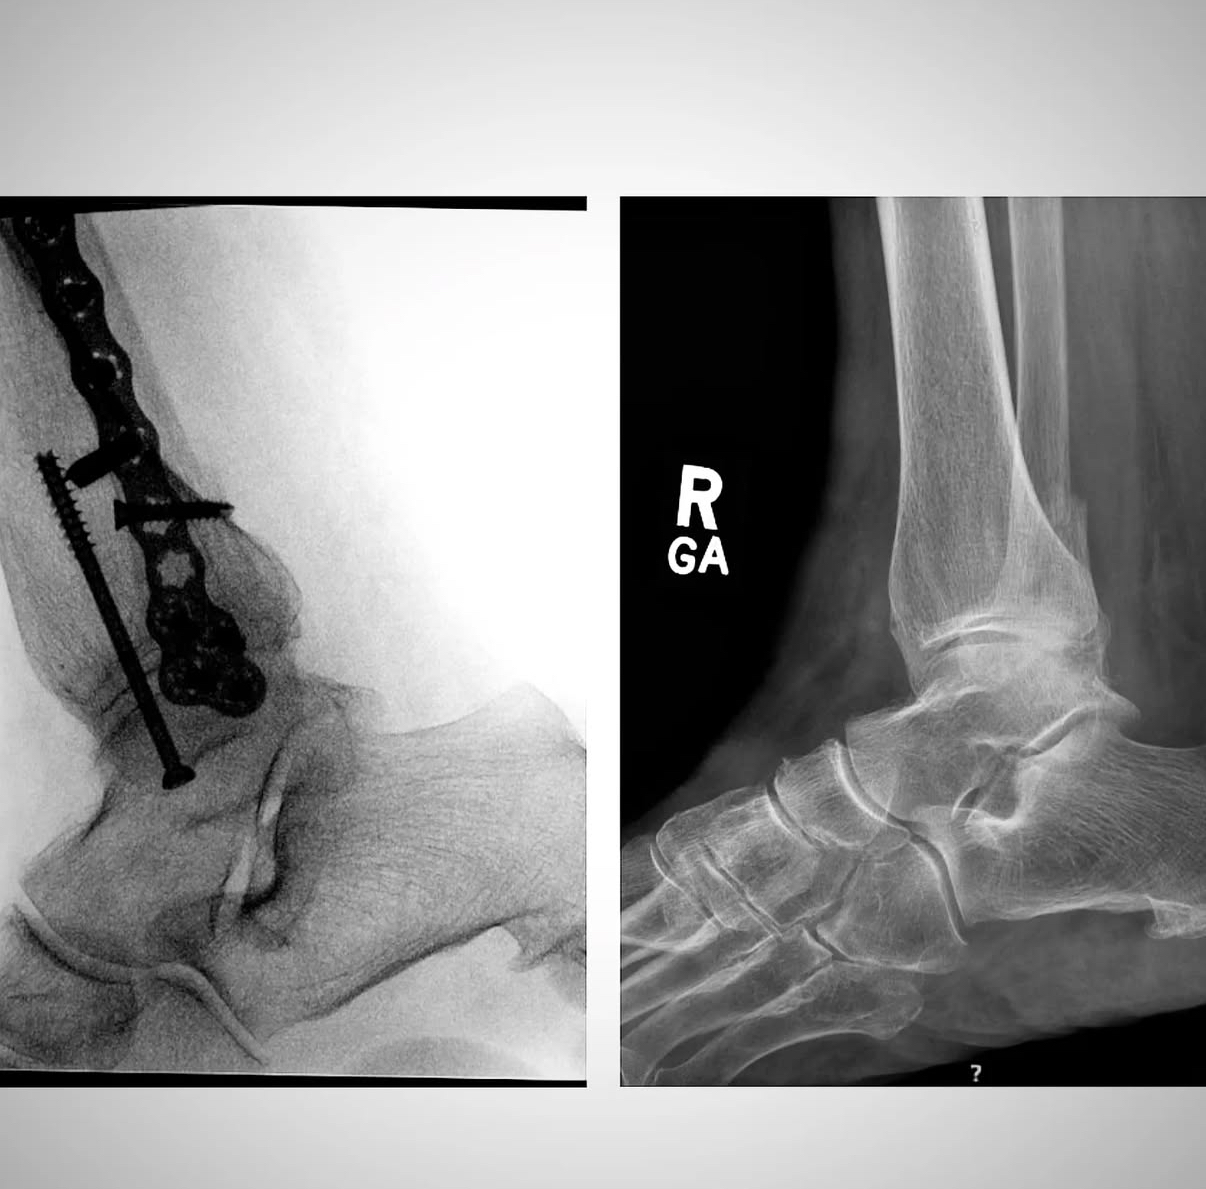

Ankle fracture repair

AF1

AF2